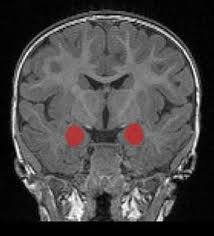

• The study examines how the development of the amygdala and caudate nucleus differs in infants with autism spectrum disorder (ASD) and fragile X syndrome, finding that amygdala enlargement appears rapidly within the first year in ASD, while caudate volume is enlarged from 6 months in fragile X syndrome, indicating disorder-specific brain development patterns.

• Researchers tracked brain growth through longitudinal MRI scans and linked early changes in amygdala growth rate to later social deficits in ASD, suggesting that the brain's structural differences develop dynamically during infancy.

• This research highlights that brain development trajectories are distinct between ASD and fragile X syndrome, with ASD-related brain changes unfolding over the first two years, whereas fragile X shows consistent early differences in the caudate from 6 months, emphasizing the importance of early diagnosis and understanding disorder-specific neurodevelopmental patterns.